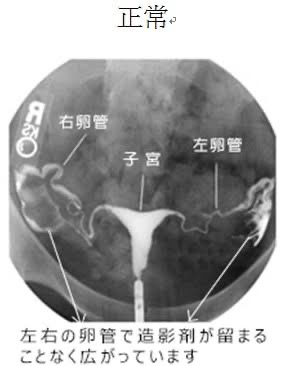

実際の子宮造影検査はこんな感じ

fu6447520.jpg

>実際の子宮造影検査はこんな感じ

このたっぷり入った造影剤はどこから排出させるんでしょうか

受けたことを後悔する痛さと聞く

>>実際の子宮造影検査はこんな感じ

人体に吸収される

造影剤は汗や尿になって流れる

普通に吸収されておしっこと排出される

卵管ってぐにゃぐにゃしてんだな